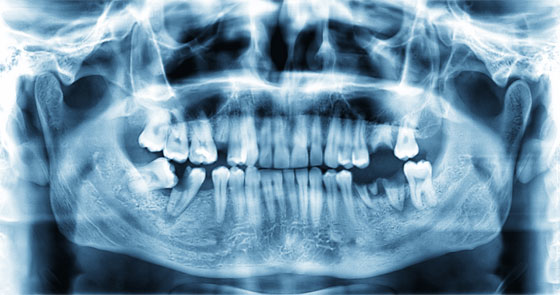

When patients refuse Xrays Registered Dental Hygienists